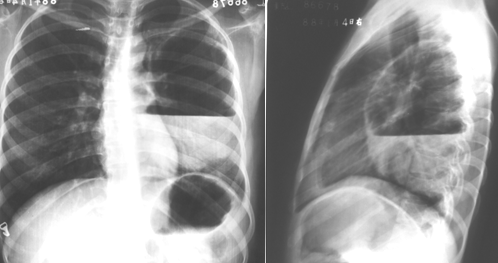

右肺下叶背段大叶性肺炎正侧位

图片

胸部正侧位片:右肺下叶背段见片状、三角形致密影,边缘模糊(箭头所指)

右肺中叶大叶性肺炎正侧位

胸部正侧位片:右肺中叶见片状致密影,边缘模糊,局部呈剪影样改变(红圈所示)